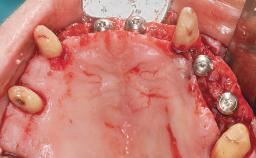

Immediate Loading of Eight Implants in the Maxilla and Six Implants in the Mandible and Final Restoration with Three-Unit and Four-Unit FDPs

Extensive scientific evidence has confirmed that immediately loaded implants with fixed full-arch provisional restorations can osseointegrate with success rates similar to conventionally or delayed loaded implants. A number of immediate-provisionalization techniques for edentulous jaws have been described. Some protocols differ when it comes to prefabricated provisional templates versus complete denture conversion; intrasurgical impressions versus direct relining; and cemented versus screw-retained provisional restorations. In this context, complete-denture conversion has been proposed for either intrasurgical impressions or direct relining. Another possibility is the utilization of a prefabricated provisional to be adapted either in the mouth (by direct relining) or in the laboratory (on a working model obtained from an intrasurgical impression).

Defining Characteristics Fully edentulous upper jaw to be rehabilitated with four or more implants

Modality 6+ implants with immediate loading

Bone Volume Horizontally and vertically sufficient